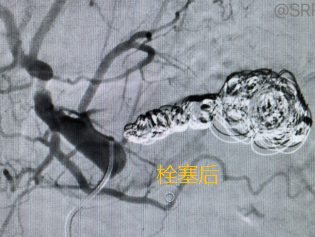

朱越锋主任和胡吉波主任共同主刀,强强联合,迅速开始进行脾动脉瘤栓塞术。

所幸的是,从穿刺股动脉、导丝选入脾动脉、微导管跟进放置弹簧圈栓塞瘤体,这些步骤一气呵成。

当以最快的速度置入 5 个弹簧圈后,造影显示脾动脉瘤血供明显减少,这时候必须乘胜追击,最后两位主任将脾动脉瘤体和供应血管彻底栓塞,造影显示瘤腔内已经完全没有血流了,这时监护仪上的心率血压也已稳定在正常范围。